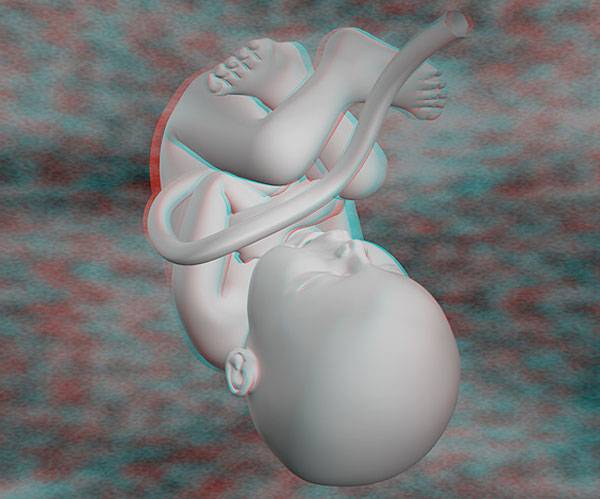

Плод 39 Недель Фото

Плод 39 Недель Фото 100 фото